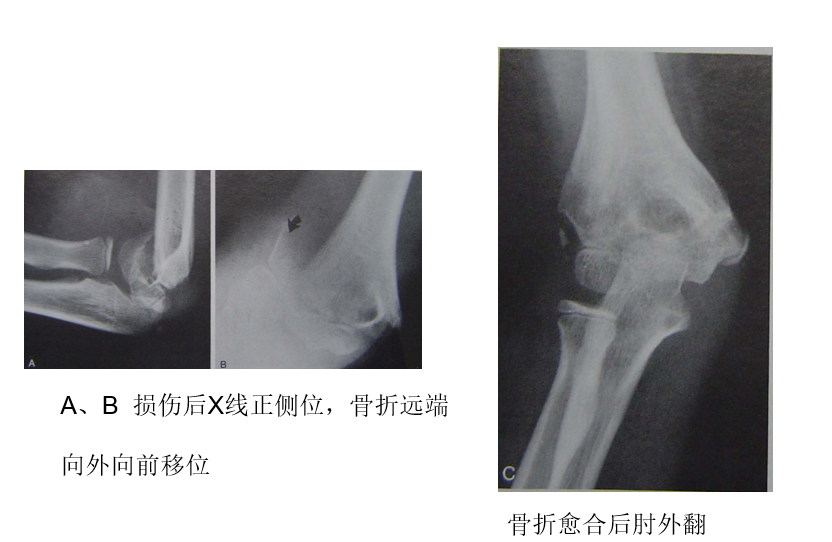

肘外翻

1  比较肘内翻,不是问题,因为正常肘关节有5~10度外翻,稍增 加,外观无妨

2  严重肘外翻不仅外观不雅,可能发生延迟性尺N麻痹